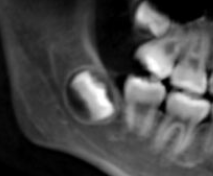

- 横向きに生える(水平埋伏)

親知らずが斜めや横向きに生えていると、手前の歯(第二大臼歯)を押して歯列を乱す原因になります。

レントゲン検査で確認した結果、親知らずが骨の中に完全に埋まっており、周囲の歯に影響しないと判断された場合は、経過観察になります。